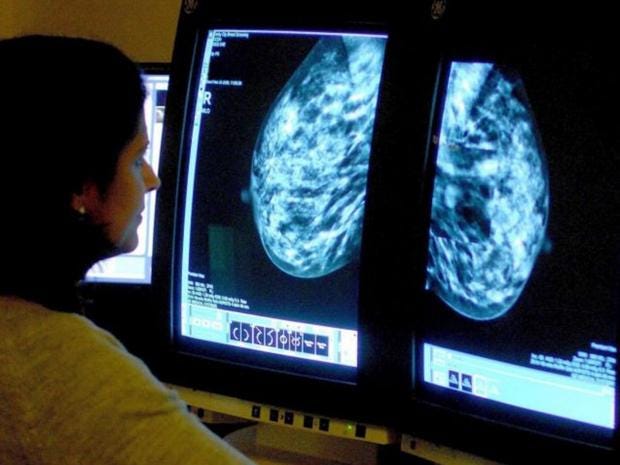

Hundreds of cancer patients may have had their chances of survival reduced after hospitals cancelled operations and tests to cope with the NHS winter crisis, an investigation has found.

Information from 81 acute trusts obtained for an investigation by the Health Service Journal (HSJ), revealed more than half said they cancelled at least one operation.

Across those 43 trusts, 530 procedures were cancelled, HSJ found. These figure includes treatment operations and diagnostic procedures such as biopsies, to see if a cancer is benign,